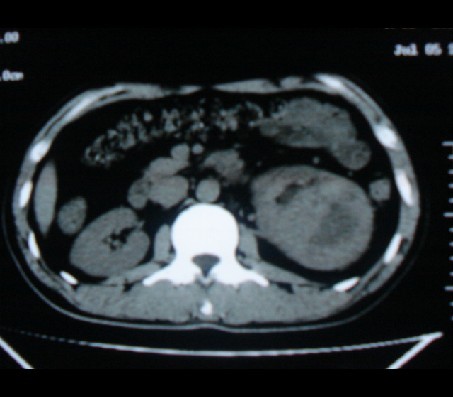

标题: CT20935:左肾占位,请会诊!

男性,35岁,ct号26189,左侧腰痛并血尿一天入院。

左肾癌侵犯肾盂可能性大,建议增强.

考虑左肾癌可能性大,建议增强扫描。

左肾癌侵犯肾盂可能性大。

肾癌侵犯肾盂,肾盂出血,肾盂内为血肿

首先考虑恶性肿瘤性病变,考虑左肾癌可能性大,建议增强扫描。